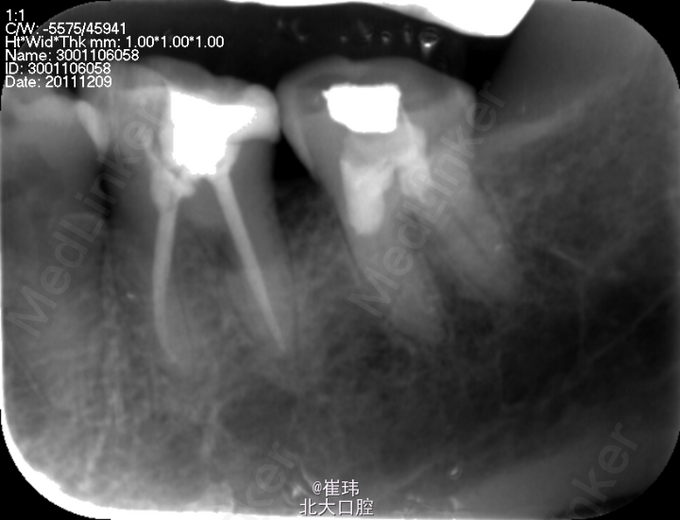

37O :银汞充填体,边缘良好,叩(±),不松,龈未见明显异常。冷测无反应。 36DO : 牙色充填体,边缘良好,叩(-),不松,龈未见明显异常。 X片示37: 充填体达根管口,未见根充影像根尖周未见明显异常 左上后牙固定修复体 27O 探及一深龋洞,色黑,质软,叩痛(+),不松,龈未见明显异常,冷测激发痛。修复科拆除26,27牙冠,拆除牙冠后见近中舌及远中颊合面深大龋洞,探敏感,质软

诊断:慢性牙髓炎急性发作